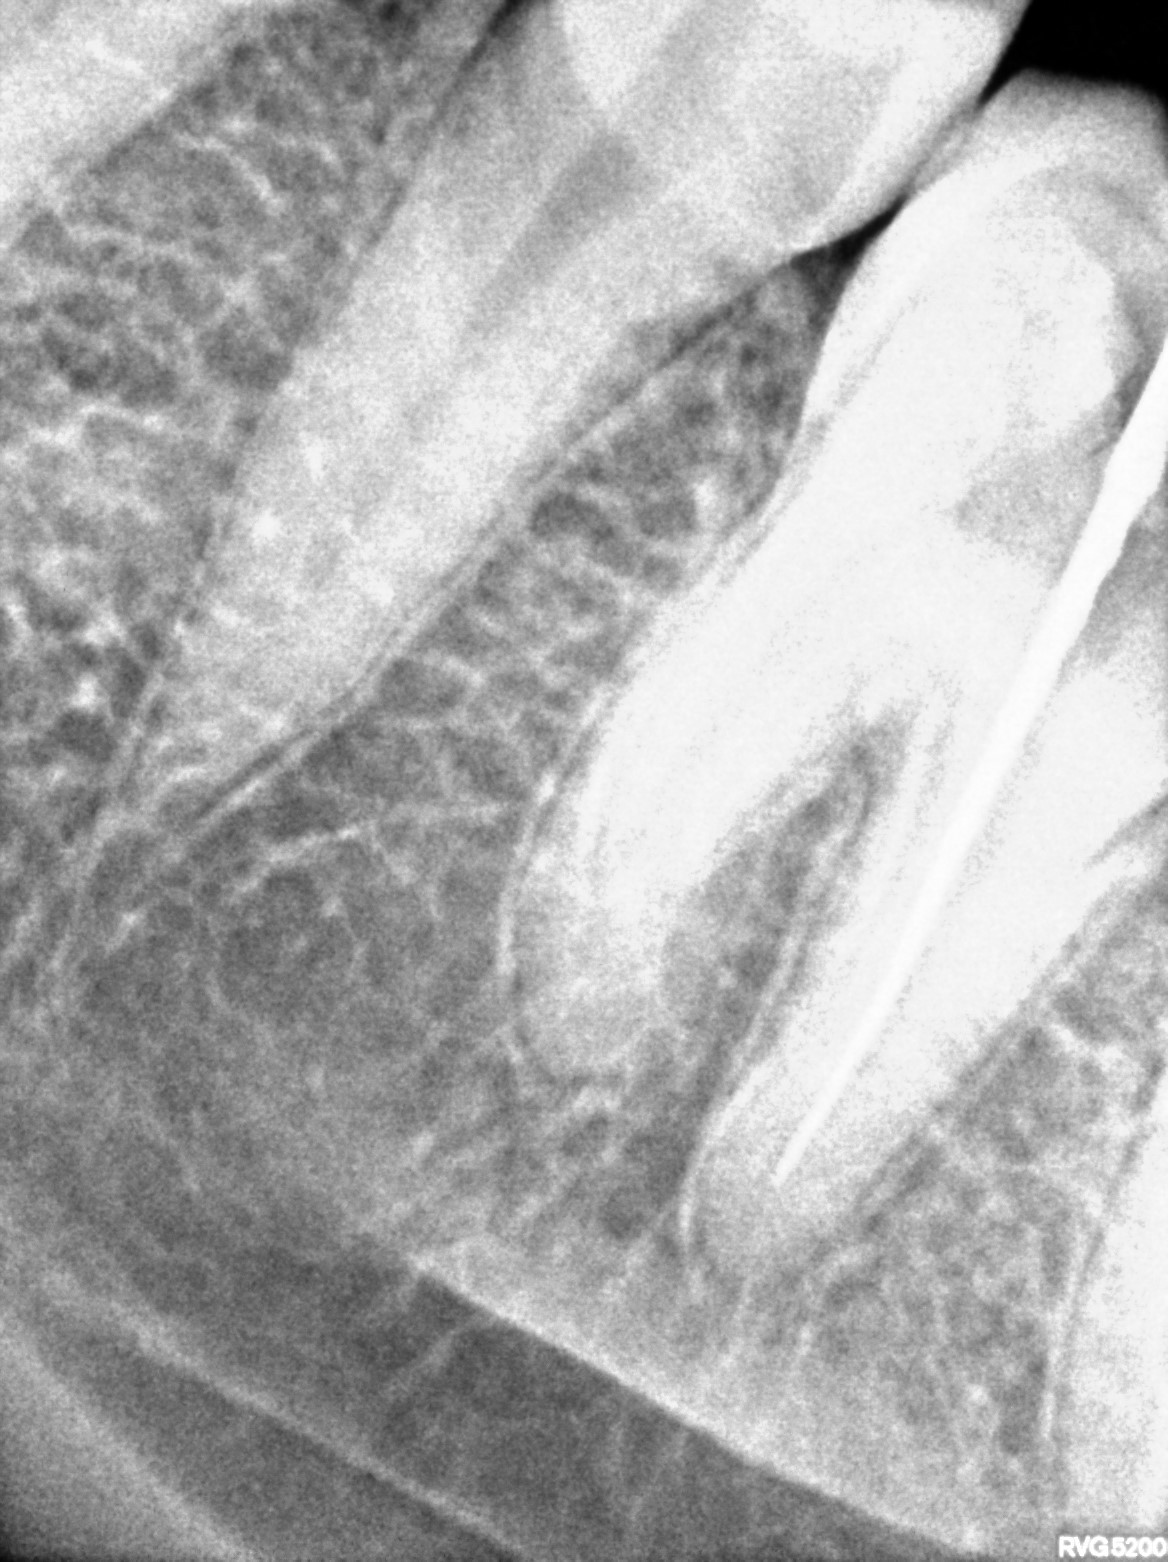

Dental Radiographs FHIR: DocumentReference · LOINC 24641-7

xray_1772180286_0.jpg

24641-7